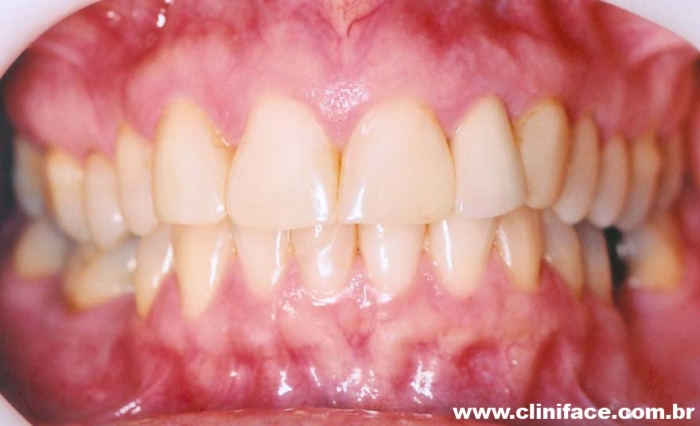

Imagem inicial e final de caso de agenesia dental, reabilitado com implante unitário no elemento 12

Prótese fixa sobre implante, finalizado em janeiro de 2010